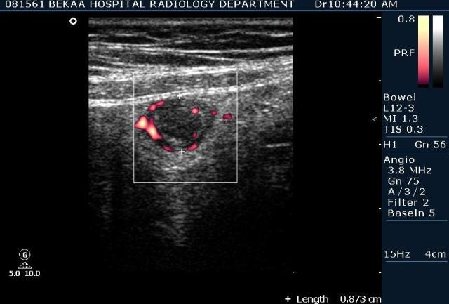

Диагностика острого аппендицита по УЗИ: очень актуальная тема; УЗ аппараты практически есть во всех клиниках; метод доступный и не сложный; главное владеть правильной техникой. Не буду загружать лишней теорией и разными ссылками; поделюсь практическим опытом. У меня линейный датчик 3-12 мегагерц с плавающей частотой; аппарат Филипс HD 11, всегда включаю соно-КТ (9800 цифровых каналов) и гармонику когда смотрю кишечник. Нормальный аппендикс видеть можно; но вопрос зачем??? Как правило, если при наличии достаточного опыта аппендикс не виден; значит скорей всего аппендицита нет. Когда "идешь" на аппендицит то главное по началу набраться терпения и......хорошая компрессия! По началу надо минут 10-15; потом когда появится достаточный опыт; за 2-5 минут можно справится и получить отличную визуализацию. Мочевой пузырь лучше опорожнить; часто он приподнимают тонкий кишечник и может закрыть "окно" через которое будет видно апендикс. Сначала находим слепую кишку потом находим илео-цекальное соединение;

после начинаем производить хорошую компрессию датчиком попрося пациента сообщить в какой точке боль наиболее выражена; медленными движениями датчика сканируем область наибольших болевых ощущений и как правило находим утолщенный отросток. Лучше начинать с поперечной визуализации и идти к верхушке аппендикса что бы убедится что это аппендикс и он заканчивается, а не тонкая кишка (которая если и закончится то только переходя в слепую); потом надо аккуратно развернуть продольно датчик и посмотреть от верхушки аппендикса к слепой. Норма диаметра: 3-4 мм; 5-6 мм под вопросом (клиника решает; но я в катаральный аппендицит не верю); 7-8 мм и больше, не компремируемый (фиксированный отросток)-острый аппендицит! Помимо наличие утолщенного аппендикса; признака "бычьего глаза" (bull-eye sign) при поперечном сканировании; надо обращать внимание на присуствие аппендоколитов в просвете; деструкцию стенки и свободной жидкости в зоне интереса.